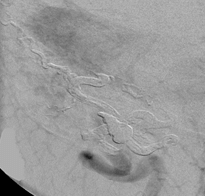

Figure 2: Dural AVF seen in figure 1 treated with glue embolization. Note the lack of an early draining vein.